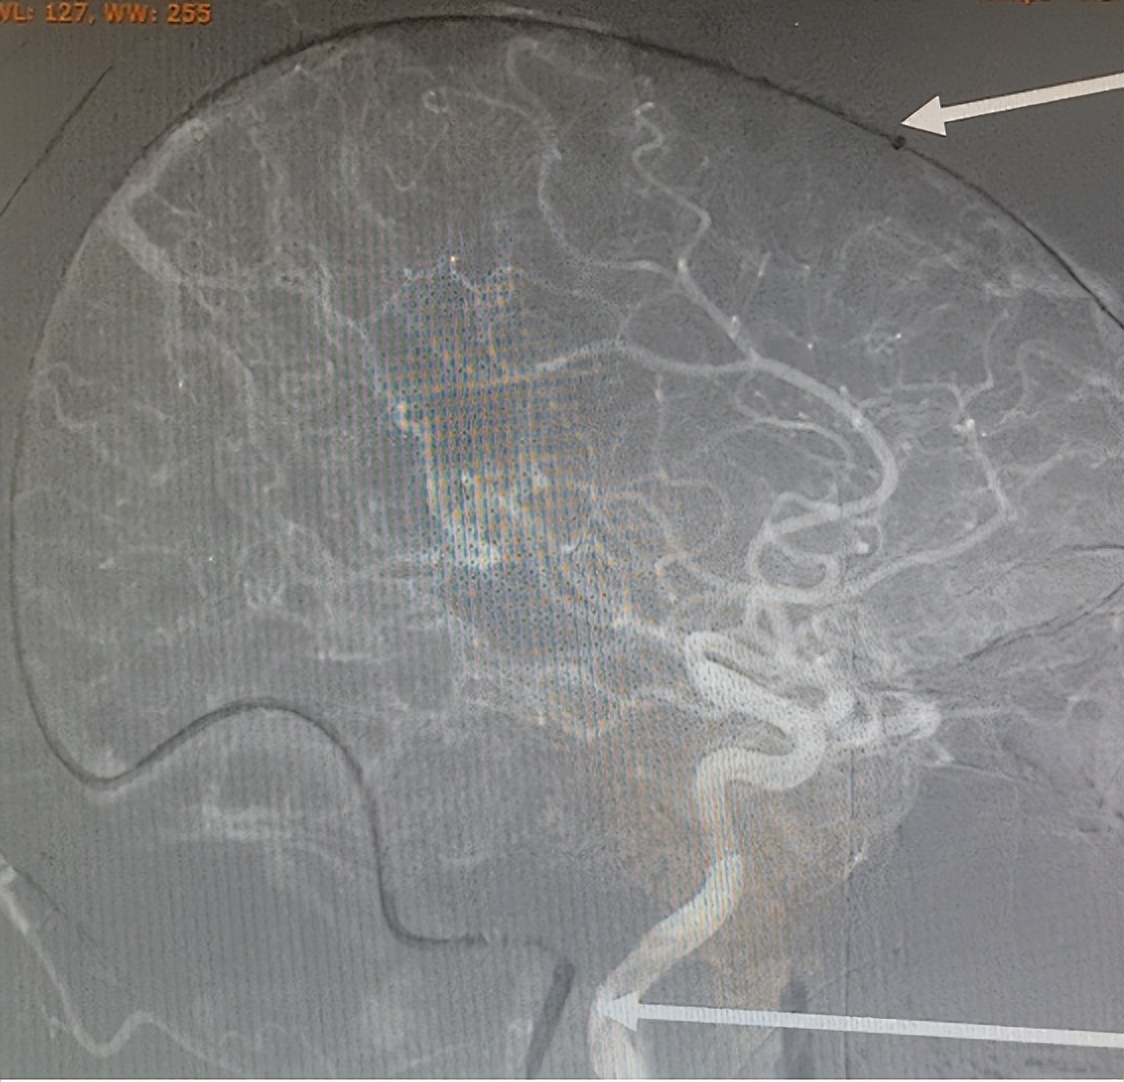

▲取栓器械到位

▲上矢状窦全程未显影

术中见“脑动静脉回流时间明显延长,上矢状窦几乎全程血栓,右侧横窦中远段及窦汇血栓,左侧横窦发育不全”,介入团队一次抽吸快速清除出颈静脉和右侧横窦的大量血栓,再通过抽吸和支架取栓技术取出了上矢状窦内的大量血栓。造影复查见“脑动静脉回流明显好转,上矢状窦、窦汇及右侧横窦、乙状窦血流通畅”。